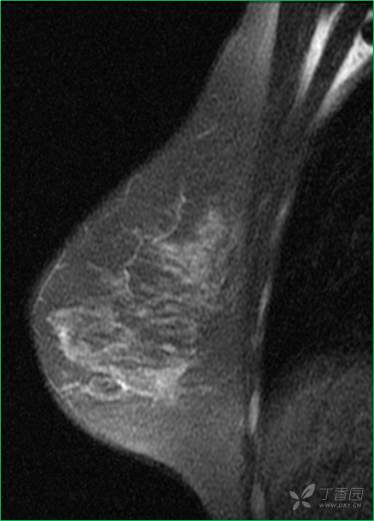

乳腺X线摄影

乳腺X线:左乳外上象限可见肿块,形态尚规则,边缘可见分叶,范围约12mm × 10mm。

乳腺MR:左乳外上象限见T2WI高信号肿块影,大小约12mm×10mm×13mm,肿块为卵圆形,边缘模糊不规则;内部强化略不均匀;TIC曲线初始相呈快速强化,延迟期呈平台型;DWI呈高信号,ADC值为 0.000698 mm2/s。

因肿块边缘不规则,内部强化不均匀, TIC曲线初始相呈快速强化,延迟期呈平台型;DWI呈高信号,ADC值较低,考虑左乳外上象限肿块恶性不除外,BIRADS 4类。